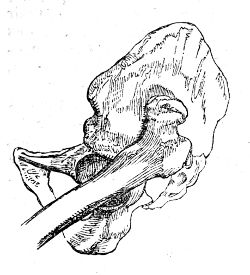

| Coxalgia | 81 |

| Alterations of Form in the Head of the Femur | 86 |